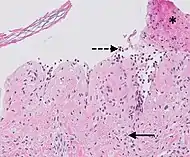

| Prevesicular stage of bullous pemphigoid | Image at right shows influx of inflammatory cells including eosinophils and neutrophils in the dermis (solid arrow) and blister cavity (dashed arrows), and deposition of fibrin (asterisks).[15] However, the diagnosis of bullous pemphigoid consist of at least 2 positive results out of 3 criteria:[19]

![]() |